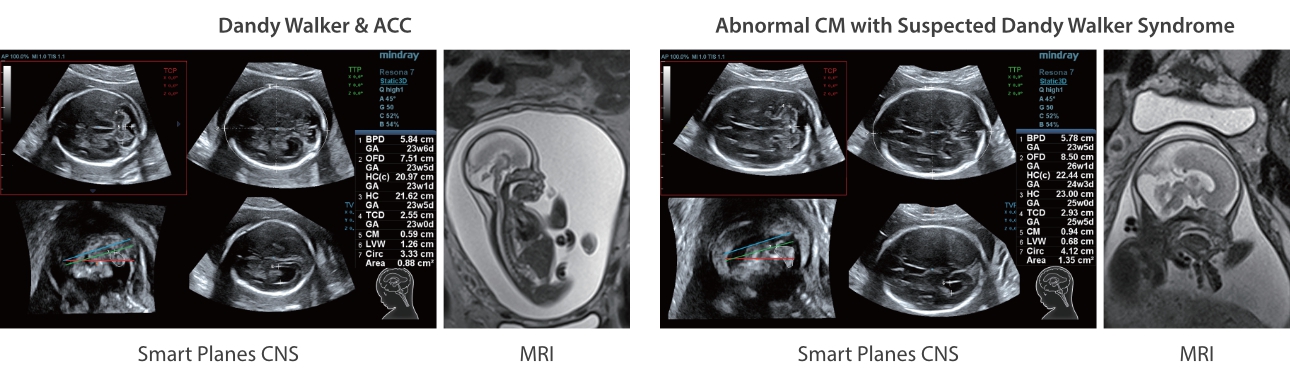

Oprócz uzyskiwania jako?ci obrazu typowego dla aparatów klasy premium, Resona 7 rozszerza mo?liwo?ci klinicznych badań USG dzi?ki rewolucyjnej funkcji V Flow, s?u??cej do oceny hemodynamiki naczyń, a tak?e najlepszej na rynku funkcji inteligentnego, automatycznego uzyskiwania p?aszczyzny na podstawie zestawów danych obj?to?ciowych 3D, umo?liwiaj?cej diagnozowanie stanu Centralnego Uk?adu Nerwowego u p?odu. Aparat Resona 7 ??czy w sobie najbardziej intuicyjn?, wielodotykow? obs?ug? za pomoc? gestów oraz wszystkie kluczowe funkcje kliniczne, co sprawia i? jest prawdziwym liderem we wprowadzaniu innowacji w ultrasonografii.